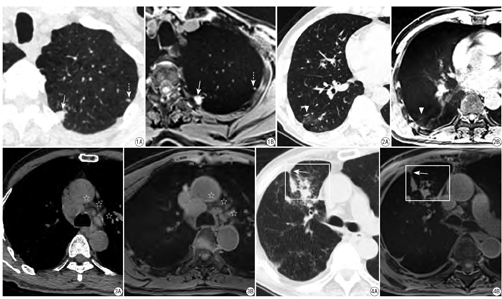

30例胸部MR及CT检查患者,CT图像共检出肺肿块(≥3 cm)16例,结节(<3 cm)137个,实变9例(范围1.3~4.2 cm),斑片状影27例(范围1.4~2.6 cm),条索状影25例(长度0.8~2.4 cm),网状影14例(范围1.5~2.6 cm),磨玻璃密度影21例(范围0.9~2.1 cm),纵隔淋巴结30例(大小5~22 mm),胸膜增厚28例(厚度3~6 mm),胸腔积液6例(少量积液),肺气肿12例,肺大泡17例,牵引性支气管扩张3例(内径7~9 mm),见图1,图2,图3,图4。

磁共振STAR-VIBE序列肺肿块、实变、纵隔淋巴结和胸腔积液的检出率均为100%,STAR-VIBE序列可以检出94.2%和92.9%的肺结节和胸膜增厚,磨玻璃密度、斑片状影、网状影、条索状影在STAR-VIBE序列的检出率依次为80.1%、85.2%、85.7%、88.0%,牵拉性支气管扩张的检出率(66.7%)高于肺气肿和肺大泡检出率,且低于其他胸部疾病征象检出率,磁共振STAR-VIBE序列无法检出肺气肿和肺大泡。详见表1、图1,图2,图3,图4。

在本研究中,采用薄层1.25 mm的CT图像作为检出各种胸部疾病征象的参考标准,STAR-VIBE序列可以检出100%的肺肿块(≥3 cm)、实变、纵隔淋巴结和胸腔积液,表明STAR-VIBE序列上肺占位、实变、纵隔淋巴结及胸腔积液的检出具有很高的准确性。肺结节和胸膜增厚在STAR-VIBE序列上的检出率高达94.2%和92.9%,STAR-VIBE序列上未检出8个直径均<4 mm的结节和2例局限性轻度胸膜增厚,这表明STAR-VIBE评价肺结节及胸膜增厚检出率与结节直径大小及胸膜增厚范围程度具有密切关系。本研究STAR-VIBE检测肺结节的检出率(94.2%)高于Cieszanowski等[10]采用T1- VIBE序列显示肺结节的检出率(80.5%)。STAR-VIBE序列显示磨玻璃密度、斑片状影、网状影、条索状影的检出率依次为80.1%、85.2%、85.7%、88.0%,这与STAR-VIBE序列虽然采用自由呼吸扫描,但自由呼吸运动和自主心脏搏动可以引起小病灶和邻近膈肌的病变显示模糊来降低检出率。牵拉性支气管扩张的检出率在STAR-VIBE序列上的检出率仅为66.7%,这可能与本研究样本中支气管扩张患者较少有关。STAR-VIBE序列无法检出肺气肿和肺大泡,这与肺组织具有低质子密度、对气体信号不敏感有关。

以CT薄层图像作为各种胸部疾病征象显示情况的主观评分参考标准,STAR-VIBE序列与CT在肺肿块(≥3 cm)、实变、纵隔淋巴结和胸腔积液的主观评分均大于4分且差异无统计学意义(P>0.05),表明STAR-VIBE序列在上述4种征象检出及评价方面可以取得与CT相似的图像质量,为临床中呼吸困难且无法屏气配合和需要长期随访观察患者提供一种可供选择的成像方式。STAR-VIBE与CT在肺结节、斑片状影、条索影、网格影、磨玻璃密度影、胸膜增厚、胸腔积液及支气管扩张等8种征象的主观评分均≥3分,表明STAR-VIBE序列在检出和显示这8种征象方面是可以提供满足临床诊断的图像质量的。但STAR-VIBE序列对8种征象的评分低于CT (P<0.05),这可能与自由呼吸状态下采集胸部数据时,肺组织自由呼吸运动、膈肌运动和心脏搏动会产生轻度伪影,从而影响各种征象显示有关。STAR-VIBE与CT对肺气肿和肺大泡的主观评分均<2分且STAR-VIBE评分显著低于CT (P<0.05),这与CT具有较高的密度分辨率,而STAR-VIBE对肺气肿和肺大泡不敏感有关。